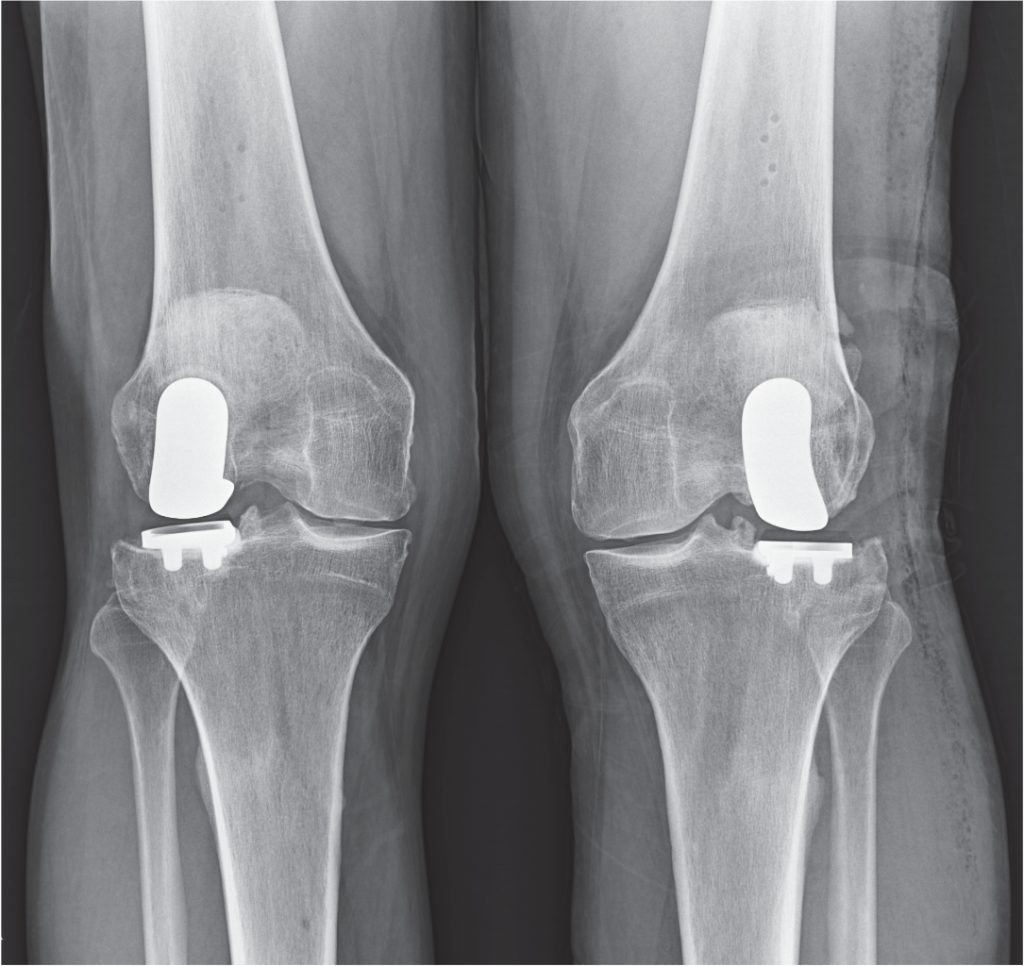

From www.reddit.com

Before/After my partial knee replacement surgery. You can see the bone Partial Knee Replacement Sports There are two types of knee replacements: Here we take a look at sports and activities that you can do after you’ve recovered from knee replacement surgery. A partial knee replacement, also known as a unicondylar knee replacement, is when only one part of the knee joint is resurfaced. After a knee replacement, playing high impact sports is possible, but. Partial Knee Replacement Sports.

From buyxraysonline.com

KNEE REPLACEMENT5 Partial Knee Replacement Sports “a partial replacement targets specific parts of the knee. There are two types of knee replacements: Here we take a look at sports and activities that you can do after you’ve recovered from knee replacement surgery. A partial knee replacement, also known as a unicondylar knee replacement, is when only one part of the knee joint is resurfaced. Learn more. Partial Knee Replacement Sports.